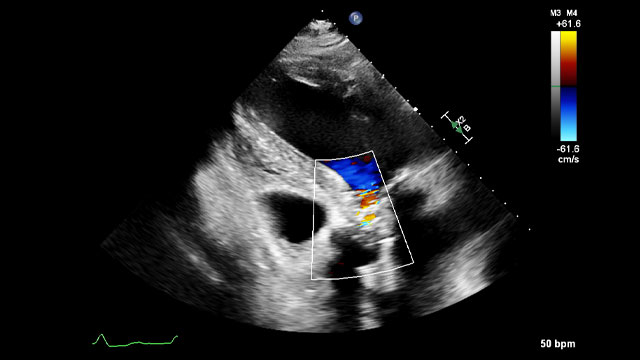

A simple maneuver to track the wire during a transseptal mitral valve-in-valve procedure

05 Nov 2025

Advancing a transcatheter heart valve through the septostomy can be tricky, with the wire sometimes prolapsing into the left atrium.

This step-by-step tutorial demonstrates a simple yet effective maneuver that allows smooth, controlled navigation from the right atrium to the mitral position, ensuring precise valve deployment.